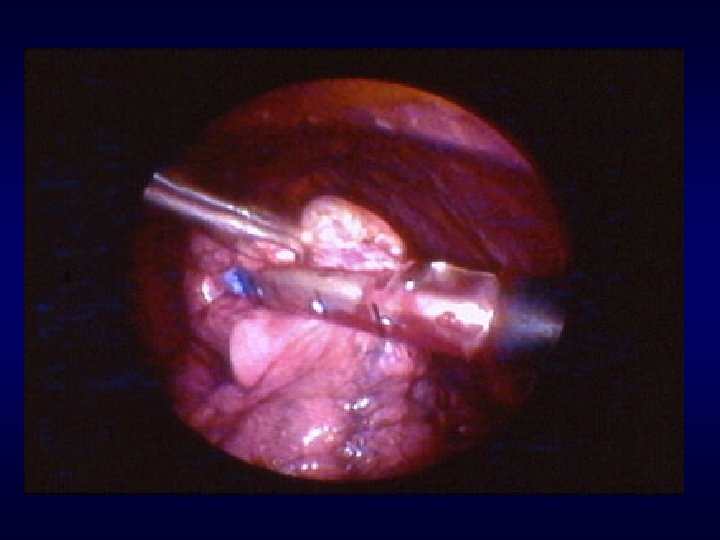

Terapia chirurgica delle bolle polmonari Bullectomia polmonare per via toracoscopica